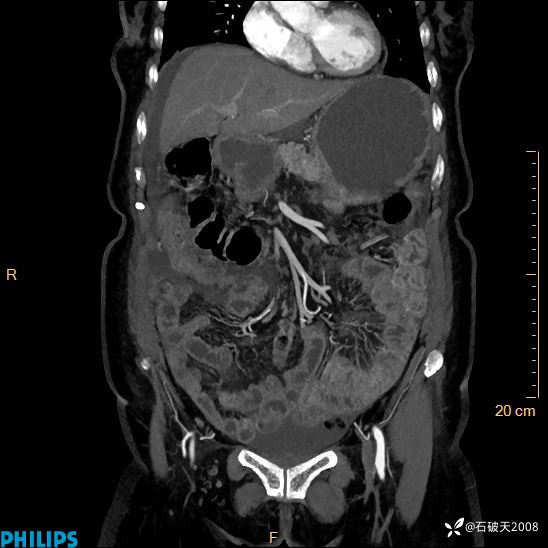

静脉期